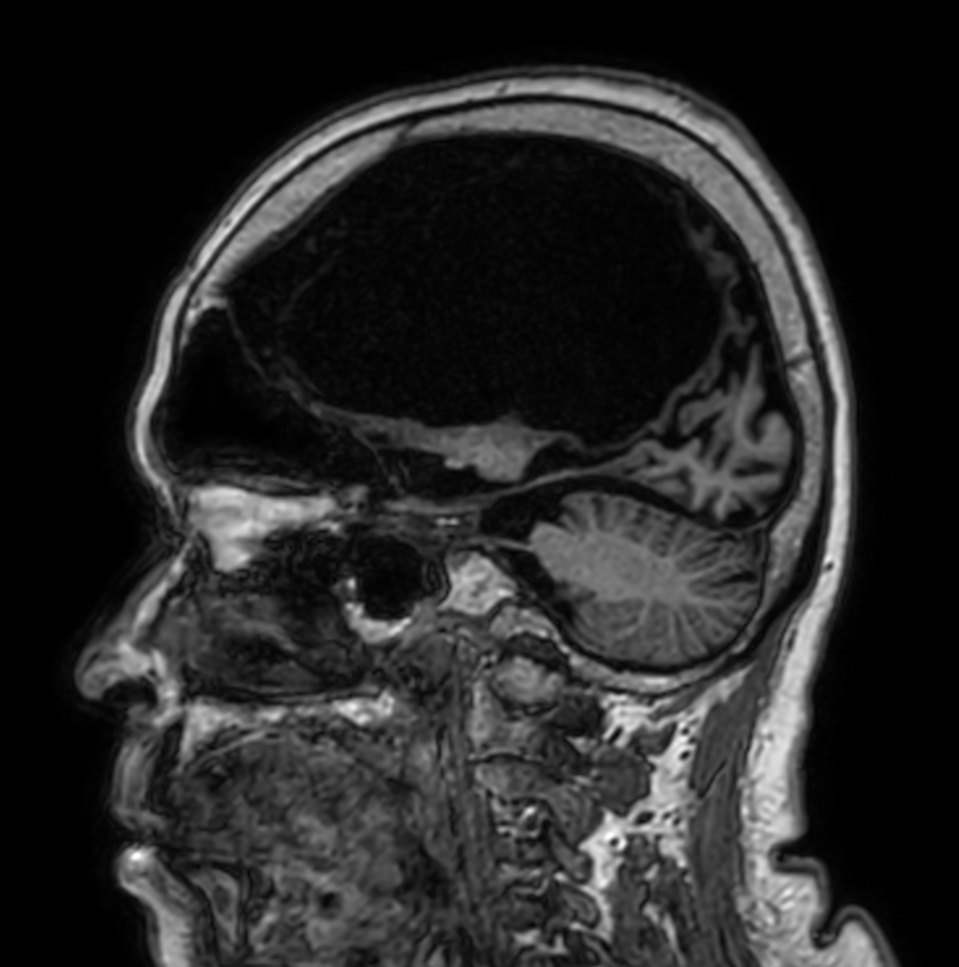

Sagittal 3D BrainVIEW FLAIR (Compressed SENSE)